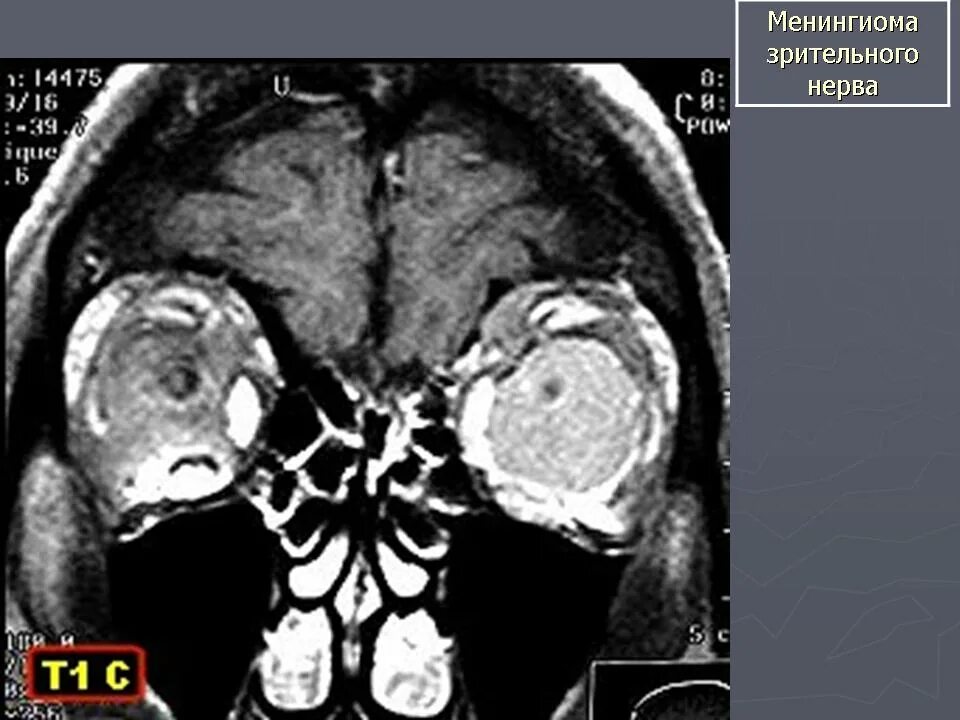

Мрт орбит и зрительных нервов